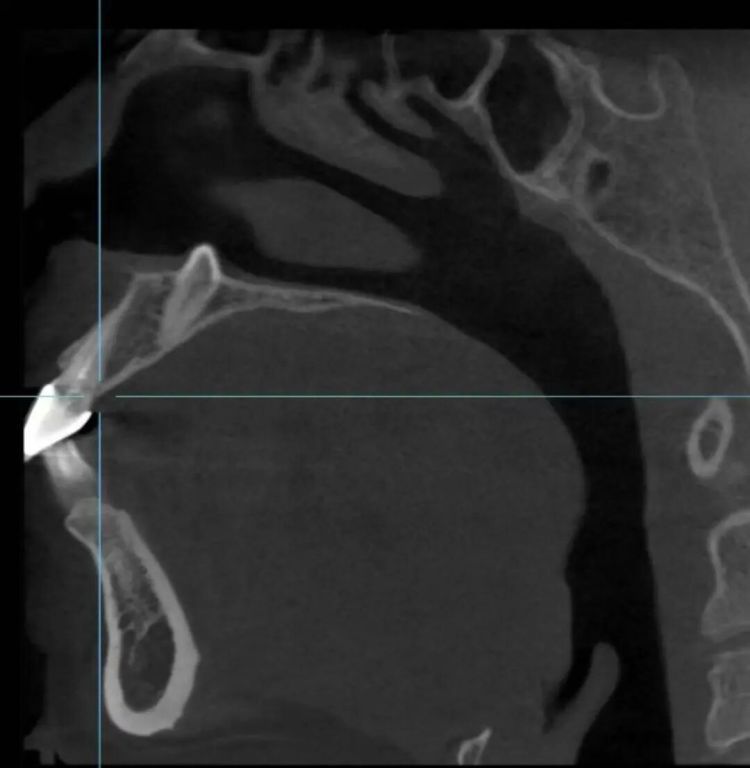

近日,高中生小郑,担心牙齿不齐被同学笑话,于是在家人的陪同下来到台州市康复医院口腔科寻求牙齿矫正治疗。在进行必要的术前影像学检查时,医生发现,小郑的门牙牙根上方、鼻腔底部的位置,竟然“埋伏”着一颗多生牙。

“这颗多生牙的牙冠向上,朝鼻腔方向伸长,牙尖已突破鼻底骨头,触及鼻底黏膜。如果不处理,在正畸移动牙齿的过程中,它会形成巨大阻碍,导致邻牙牙根吸收、正畸失败,甚至可能在未来穿破鼻腔,影响健康。”台州市康复医院口腔科主任医师戴杰介绍。

“其实,这是一种被称为‘埋伏多生牙’的情况。多生牙,顾名思义,就是正常牙列数目之外长出来的牙齿,可能出现在颌骨的任何部位,最常见于上颌前牙区。”戴杰解释道,发育过程中,该患者多生牙的牙胚不像正常牙齿一样向下萌出,而是“迷了路”,朝相反方向——即鼻腔底部生长,“由于上颌骨前牙区上方紧邻鼻腔,这才形成了逼近鼻腔的特殊位置。”